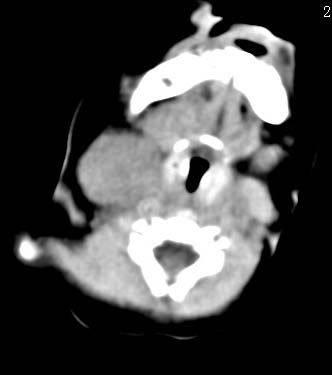

以下是引用zjzjr在2008-12-18 11:20:00的发言:[br]右颈部软组织肿块,性质待定(神经源性肿瘤等排),上下径较长,不太支持肿大淋巴结.